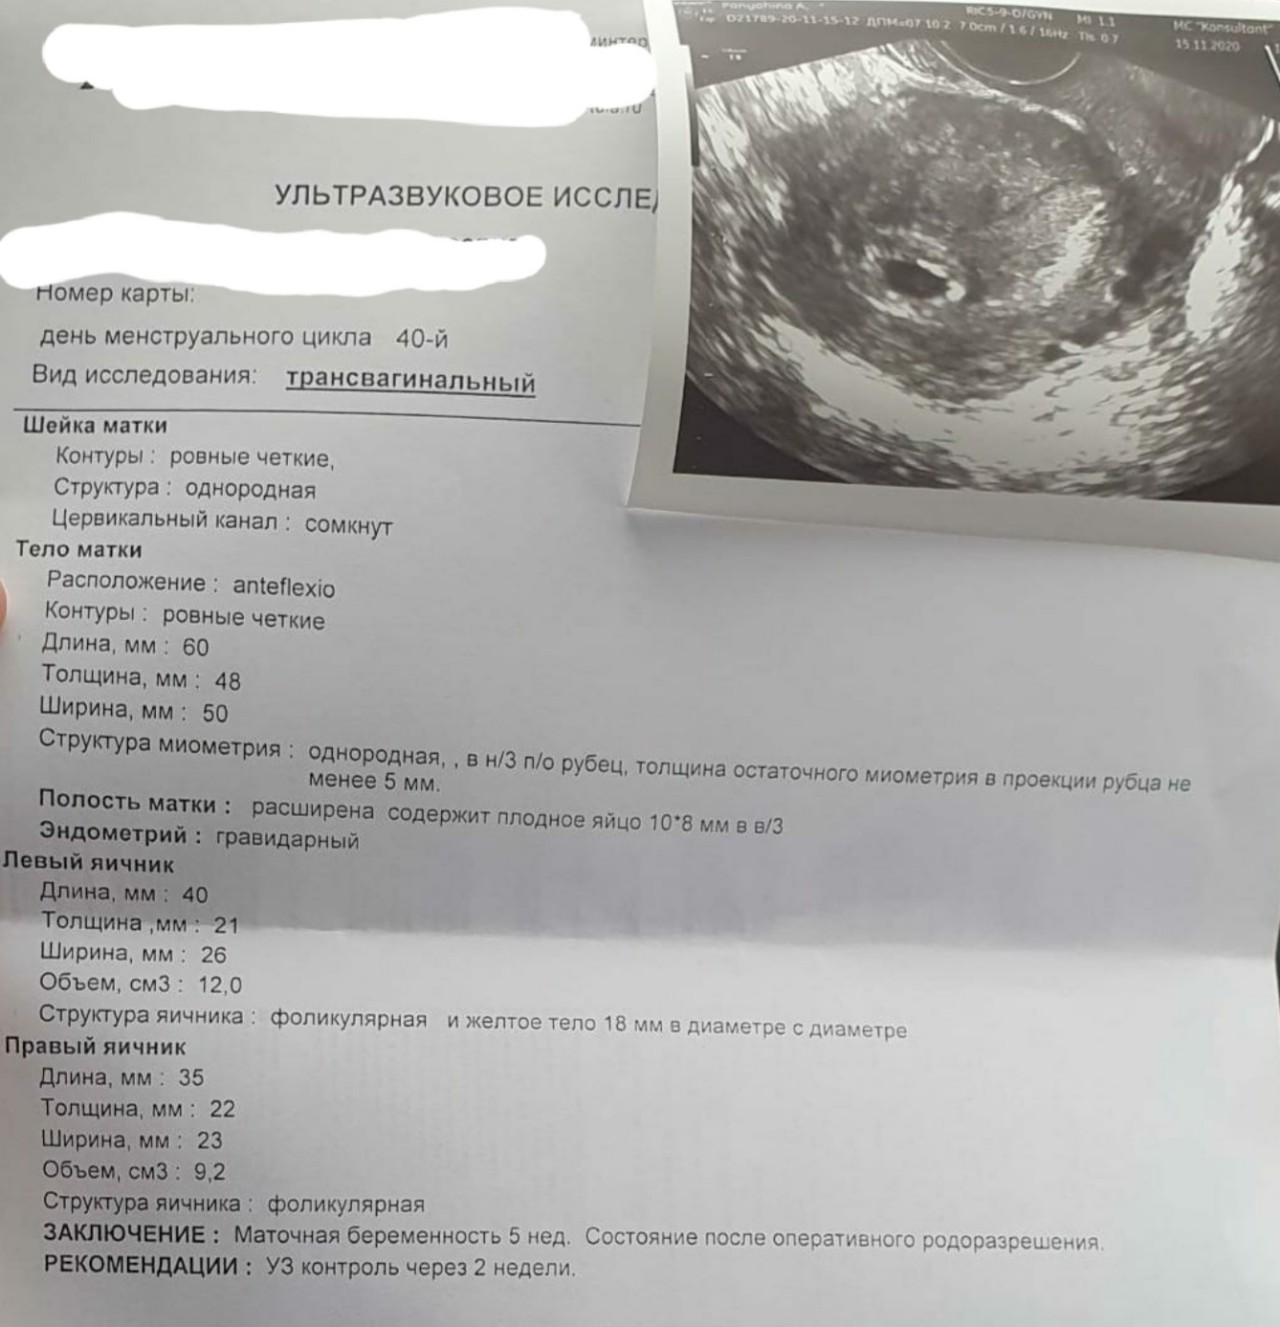

Акушерские недели беременности: особенности и расчёт сроков

Раздел: Идеи и советы